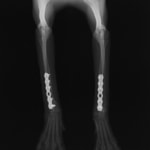

トイプードル 右遠位橈尺骨短斜骨折のALPSによる内固定

Locking Compression Plate

LCPは、スクリュー(ネジ)とプレート(金属の板)をロックする特殊な構造により骨折部位を固定する新しい世代のプレートシステムです。ひとつのホールでロッキングスクリューとスタンダードスクリューの使用を選択できるユニークな構造をしているため、骨折断端間の圧迫を目的とした従来型プレート固定法に加え、高い角度安定性を有するロッキングスクリューを用いた固定法の選択が可能です。従来のプレートシステムでは困難だった部分の骨折や癒合不全の症例に高い治療効果をもたらします。

Locking compression plate system の特徴

1.骨膜上の血行障害は最小限

2.高い角度安定性

3.プレート設置時の整復位喪失の防止

4.スクリューのルースニング(ゆるみ)の防止

5.コンビネーションホール

6.粗鬆骨における固定性の向上

7.1.5mmと薄いプレートのため、超小型犬にも使用しやすい

8.抜去が不要となることが多い